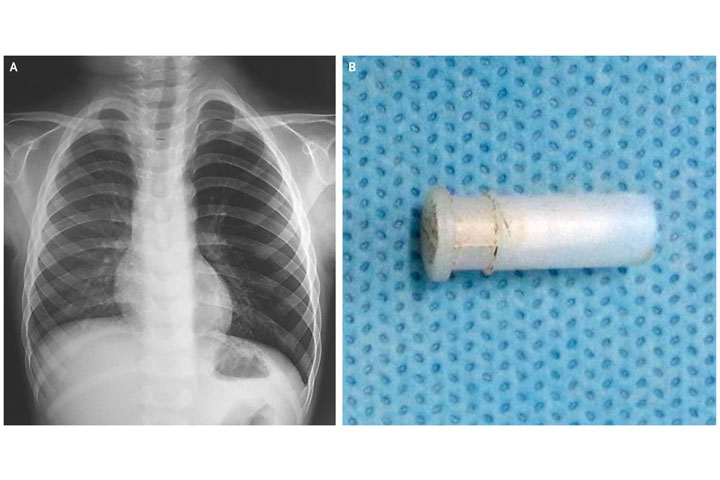

So doctors took an X-ray of the boy’s chest. This is when they started to narrow in on the problem. The boy’s left lung was hyperinflated – a sign that the air wasn’t getting out properly, which is often caused by a foreign object in the lung. Although they couldn’t see what was in there, they decided to go in.

Radioscopy of a four-year-old boy showing hyperinflation of his left lung (left). On the right, the cause of his cough. New England Journal of Medicine

They performed a rigid bronchoscopy, sliding a camera and instrument into the boy’s airway to take a look. They came out with a white plastic toy whistle that was lodged in the boy’s lung.

Thankfully, another X-ray taken the next day showed that the boy’s lung was back to normal. A year later, he was still doing fine, though maybe was more careful around whistles.